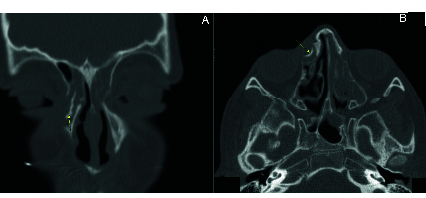

Case report: A nine-year-old girl presented with intermittent unilateral hemolacria and episodes of dacryocystitis with no further remarkable medical or surgical history. CT scan indicated the presence of well-defined calcified tissue enclosed within the lacrimal sac. Following external dacryocystorhinostomy, well-formed firm tissue resembling bony tissue was extracted and sent for pathological evaluation, along with biopsies from the lacrimal sac. Histopathological analysis revealed heterotopic bone formation with nonspecific inflammation of the lacrimal sac. No underlying cause was discernible in the complementary assessment, and no recurrence was noted at one-year follow-up.